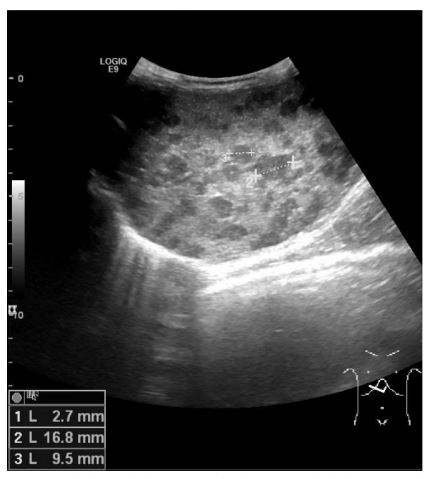

Figure 3 CT-scan showing multiple hepatic metastases and increased left adrenal volume (arrow) suggesting a primary tumour arising from the left adrenal gland

Thoracoabdominal computed tomography (CT) (Fig. 3) showed an enlarged left adrenal gland (15mm), along with the previously identified hepatic lesions, suggesting a primary tumour arising from the left adrenal gland with secondary liver metastasis. Bone marrow aspirate and biopsy (performed for staging) showed no abnormalities.